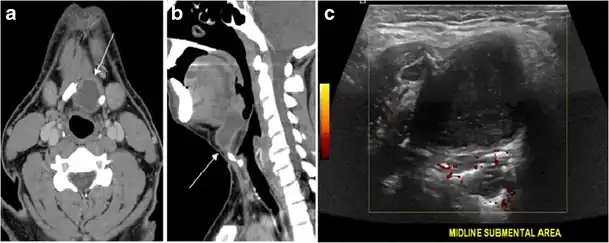

Fig. 17. Ectopic thyroid on the left parotid gland with a palpable left parotid mass in a 69-year-old male patient. a, b Axial and coronal enhanced neck CT scan demonstrates well-defined homogeneous enhancing mass (white arrows) within the left parotid gland with preserved surrounding fat planes. It also shows a normal thyroid in normal position in the lower neck. c Image taken 20 minutes after 5 mCi injected Tc99m-Pertechnetate shows normal thyroid uptake of tracer and physiological uptake in the salivary glands (short black arrow). There is a distinct focus of abnormal tracer accumulation in the left parotid/submandibular region. Patient was given lemon juice with evident normal washout from the salivary glands and relative retention by this abnormal focus (long black arrow).[1] -